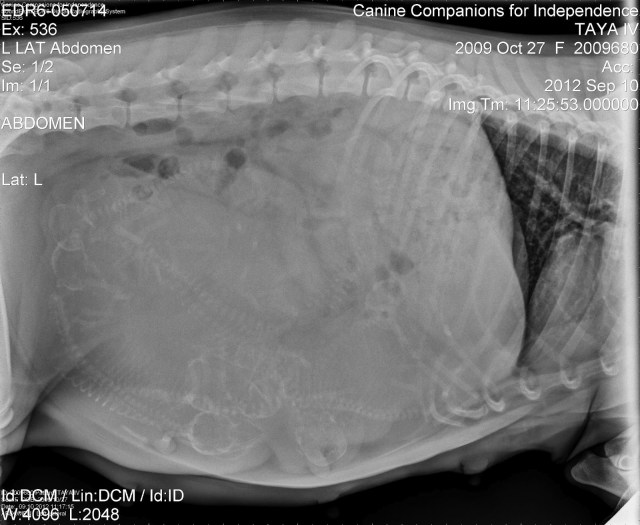

| Photo courtesy Canine Companions for Independence and Eukanuba |

Puppies, they are a’cookin. Taya shows us her upcoming E litter for Canine Companions for Independence. How many do you see in there?

However many, each of these tiny images will be born in the world with the destiny of being someone’s miracle. Assistance dogs in the making, rather literally.